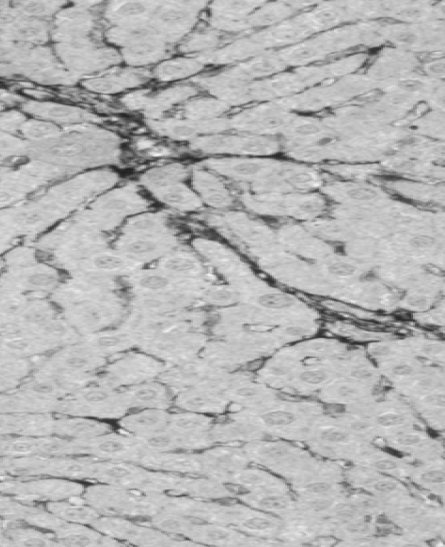

Animal trials are a crucial step in evaluating the safety and efficacy of novel medical products. In a rat model of severe liver failure, our combined stem cell & exosome therapy successfully repaired liver damage—an effect absent in the control group. While 40% of untreated subjects succumbed, 100% of those treated survived, highlighting both the regenerative and life-saving potential of our product.

This achievement was accepted as a poster presentation at the American Association for the Study of Liver Diseases conference (Nov 2024), with human trials set to begin in Q1 2025.

Liver damage with fibrosis

Before

After